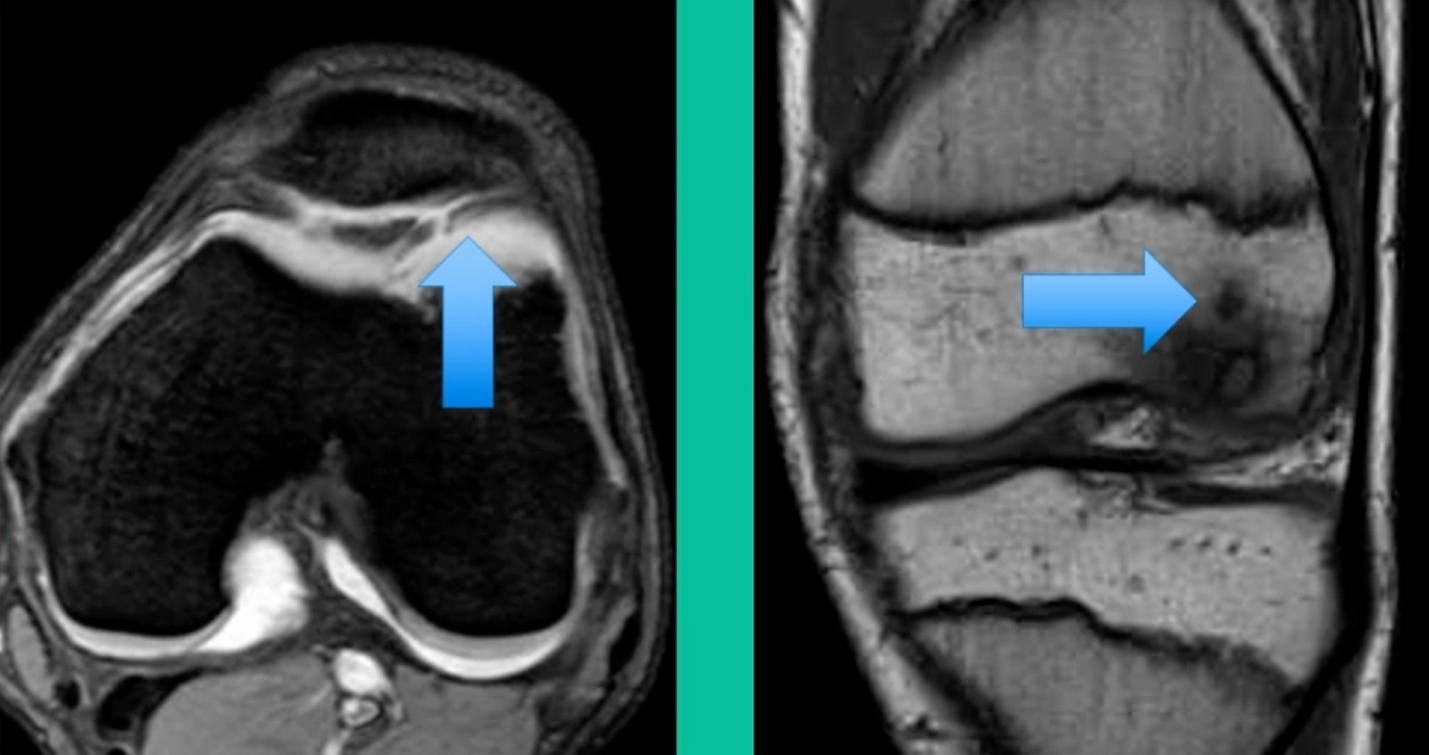

The only other thing to know is about stability. This is probably the most important physiology tenet. This is a biologic problem, because it’s a fracture non-union. But it’s a biomechanical problem because they’ve got a pebble in their shoe when they become symptomatic. So, we talk about the MRIs showing stability. The reality is if they hurt, they probably have microscopic instability. The challenge is if you take a microscopic versus a macroscopically unstable one, the treatment will differ.

Who’s going to heal in the young group? It’s going to be someone who’s much younger. Non-weight-bearing location. Lateral aspect of the medial femoral condyle can often be non-weight-bearing. Smaller lesions, no MRI signs of gross macro-instability, and the absence of sclerosis in cysts. These might heal.

Now a couple of quick cases. This is juvenile OCD. This is the first series of three or four, just juveniles. 14-year-old, intermittent knee pain, lateral femoral condyle OCD (Figure 1).

This is an 11-year-old. Left knee lateral knee pain. Effusions, the same type of classic findings (Figure 3)

You look at this one, you say, “what are you going to see when you get in there?” This is one when you get in there, you say, I’m not even sure I’m in the right knee because you almost don’t see it. That happens in patients who were painful, but they don’t look macroscopically unstable. Pediatric orthopedic surgeons tend to drill these. These are the ones that I see as failures. I think when you’re talking about something that’s mechanically unstable, it’s hard to understand why drilling would actually make it work without fixation. Even if it’s microscopically unstable.